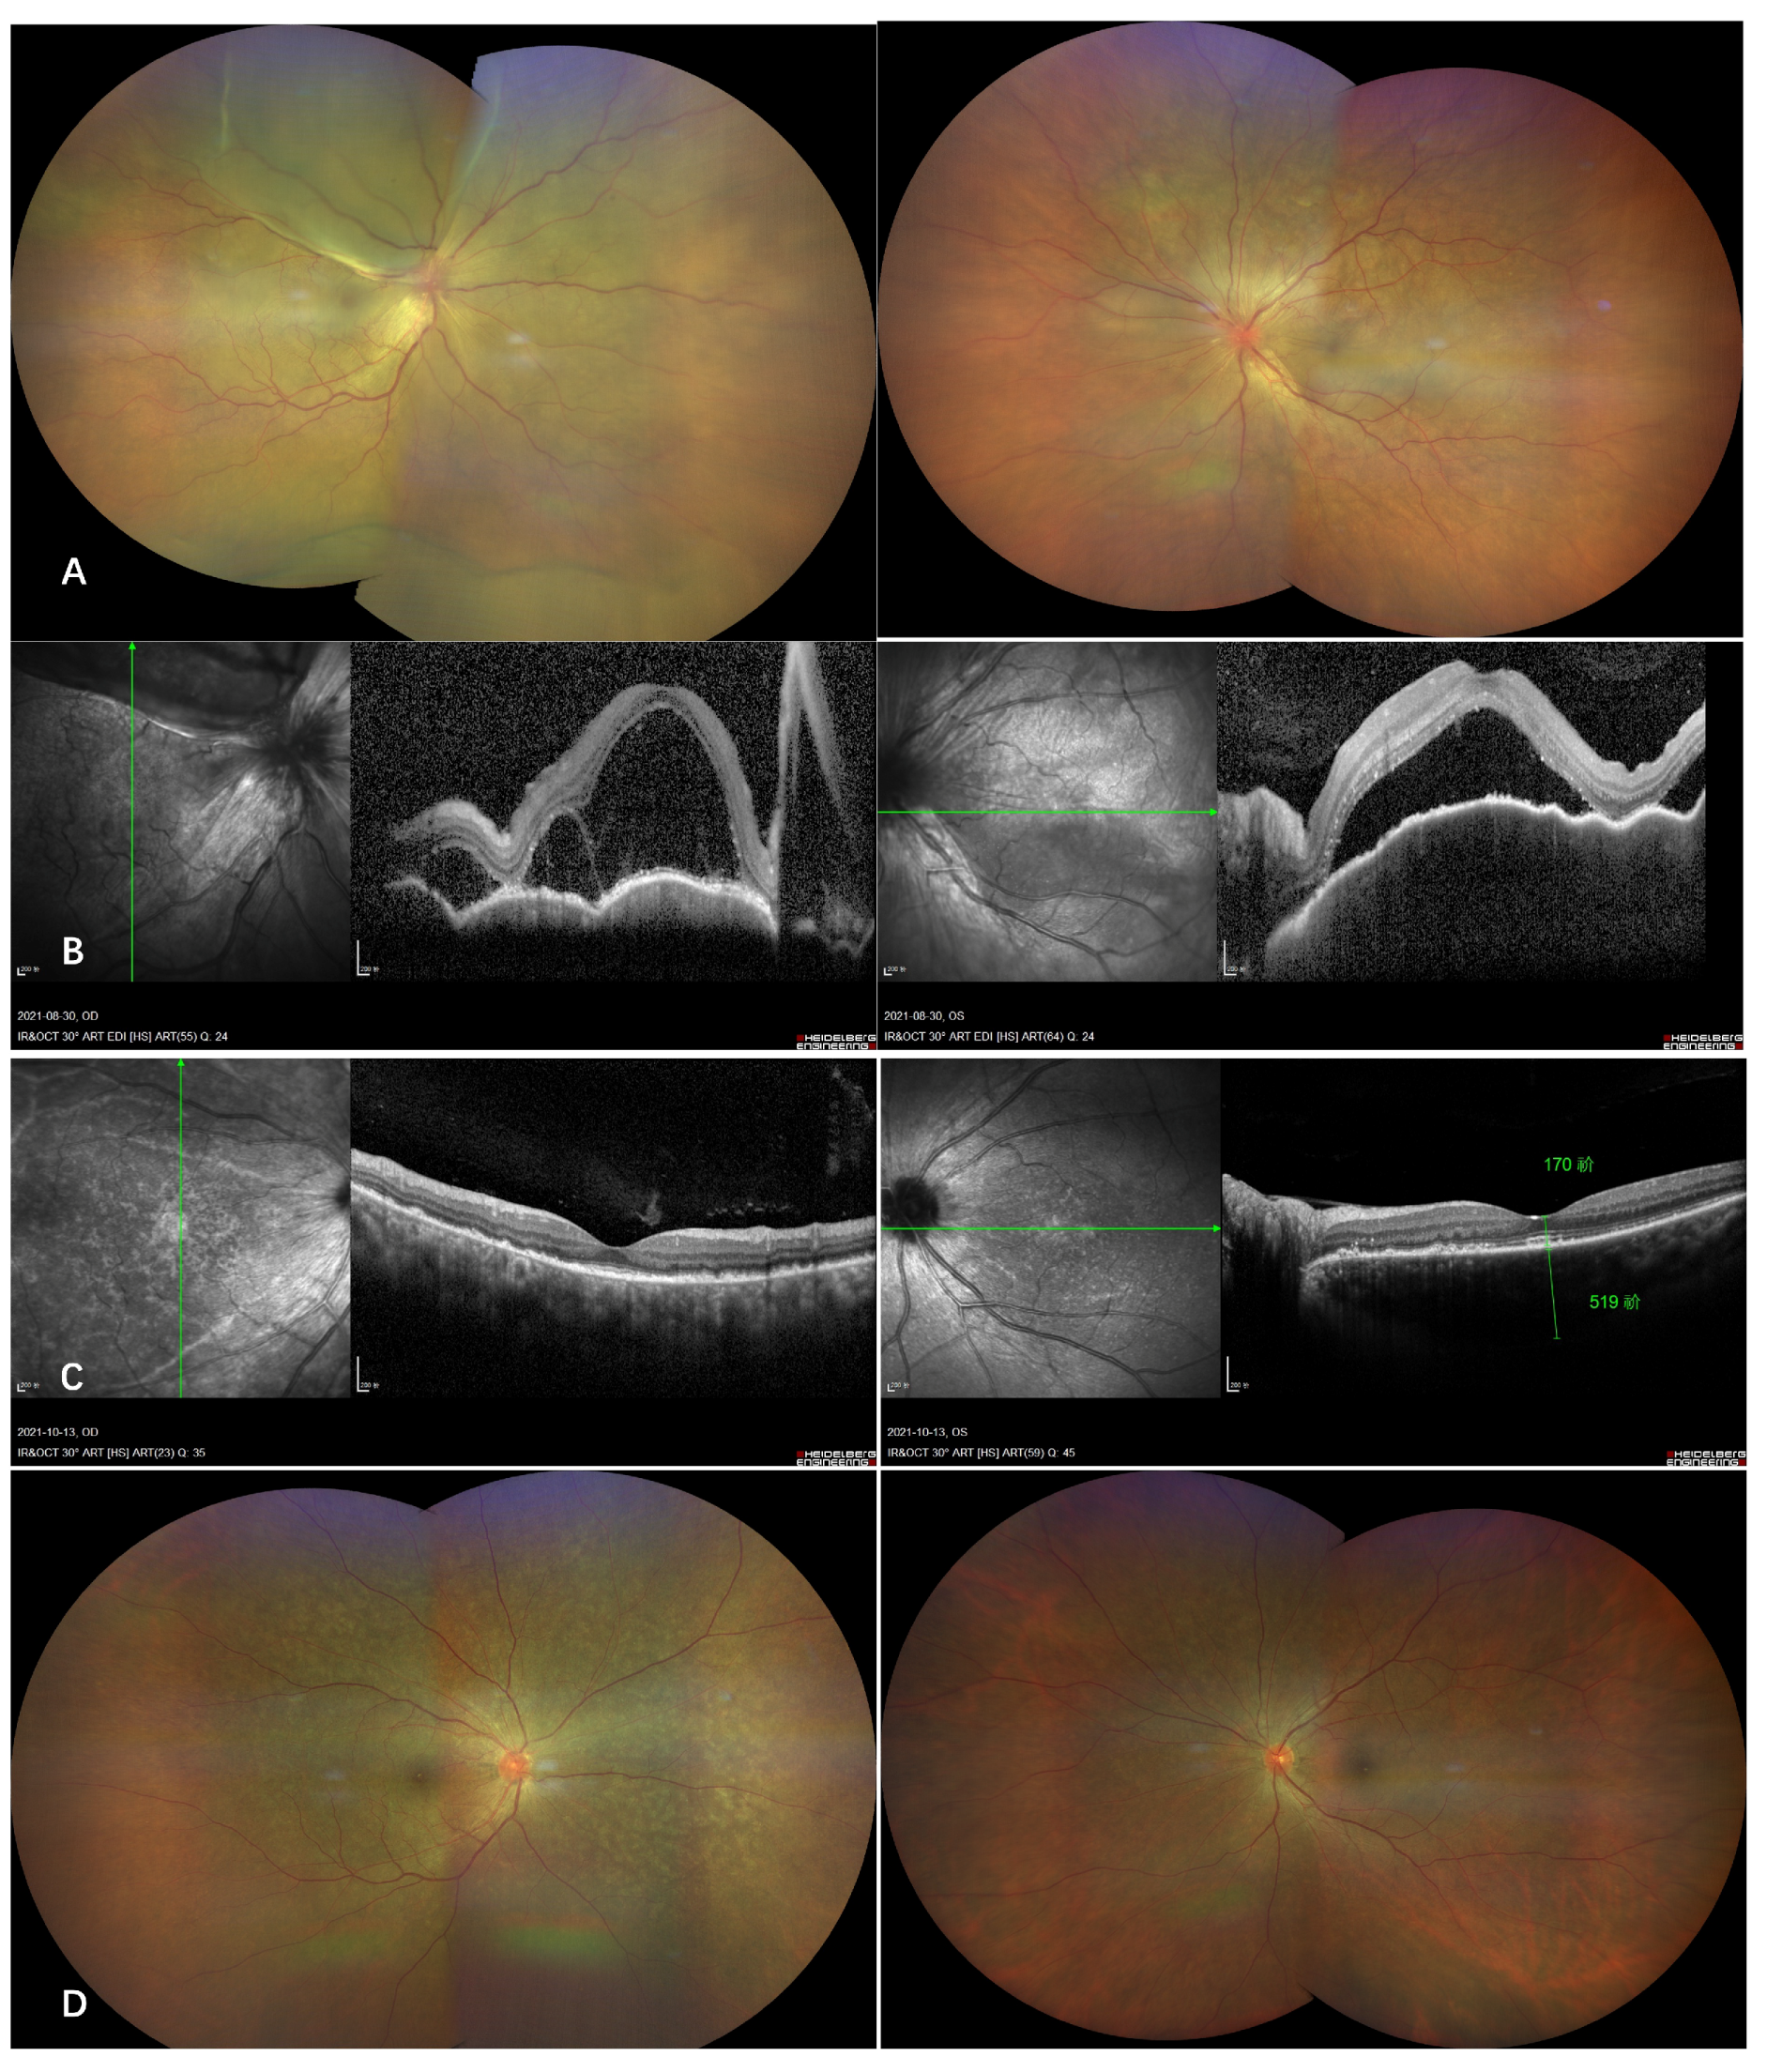

Selected Cases

- Case 1

- Case 2

- Case 3